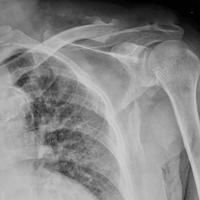

X線照片檢查、CT掃描和CT三維結構重建可清晰顯示肩胛骨骨折。診斷

3.影像學檢查

要求清晰的X線平片(前後位、側位及切線位),大多可獲得確診,對診斷困難者可藉助於CT掃描;在影像學檢查中尚應注意有無胸部伴發傷。